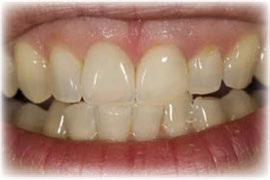

Figuras 18-21. Imágenes iniciales y finales de la paciente a los dos años de seguimiento donde observamos el cambio de la sonrisa y la recuperación de la dimensión vertical realizada con la rehabilitación sobre implantes y la confección de nuevas prótesis sobre implantes en el primer cuadrante y facetas en los sectores anteriores superiores e inferiores.